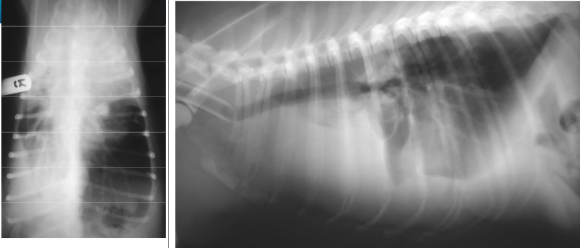

• whats the diagnosis?

pneumothorax